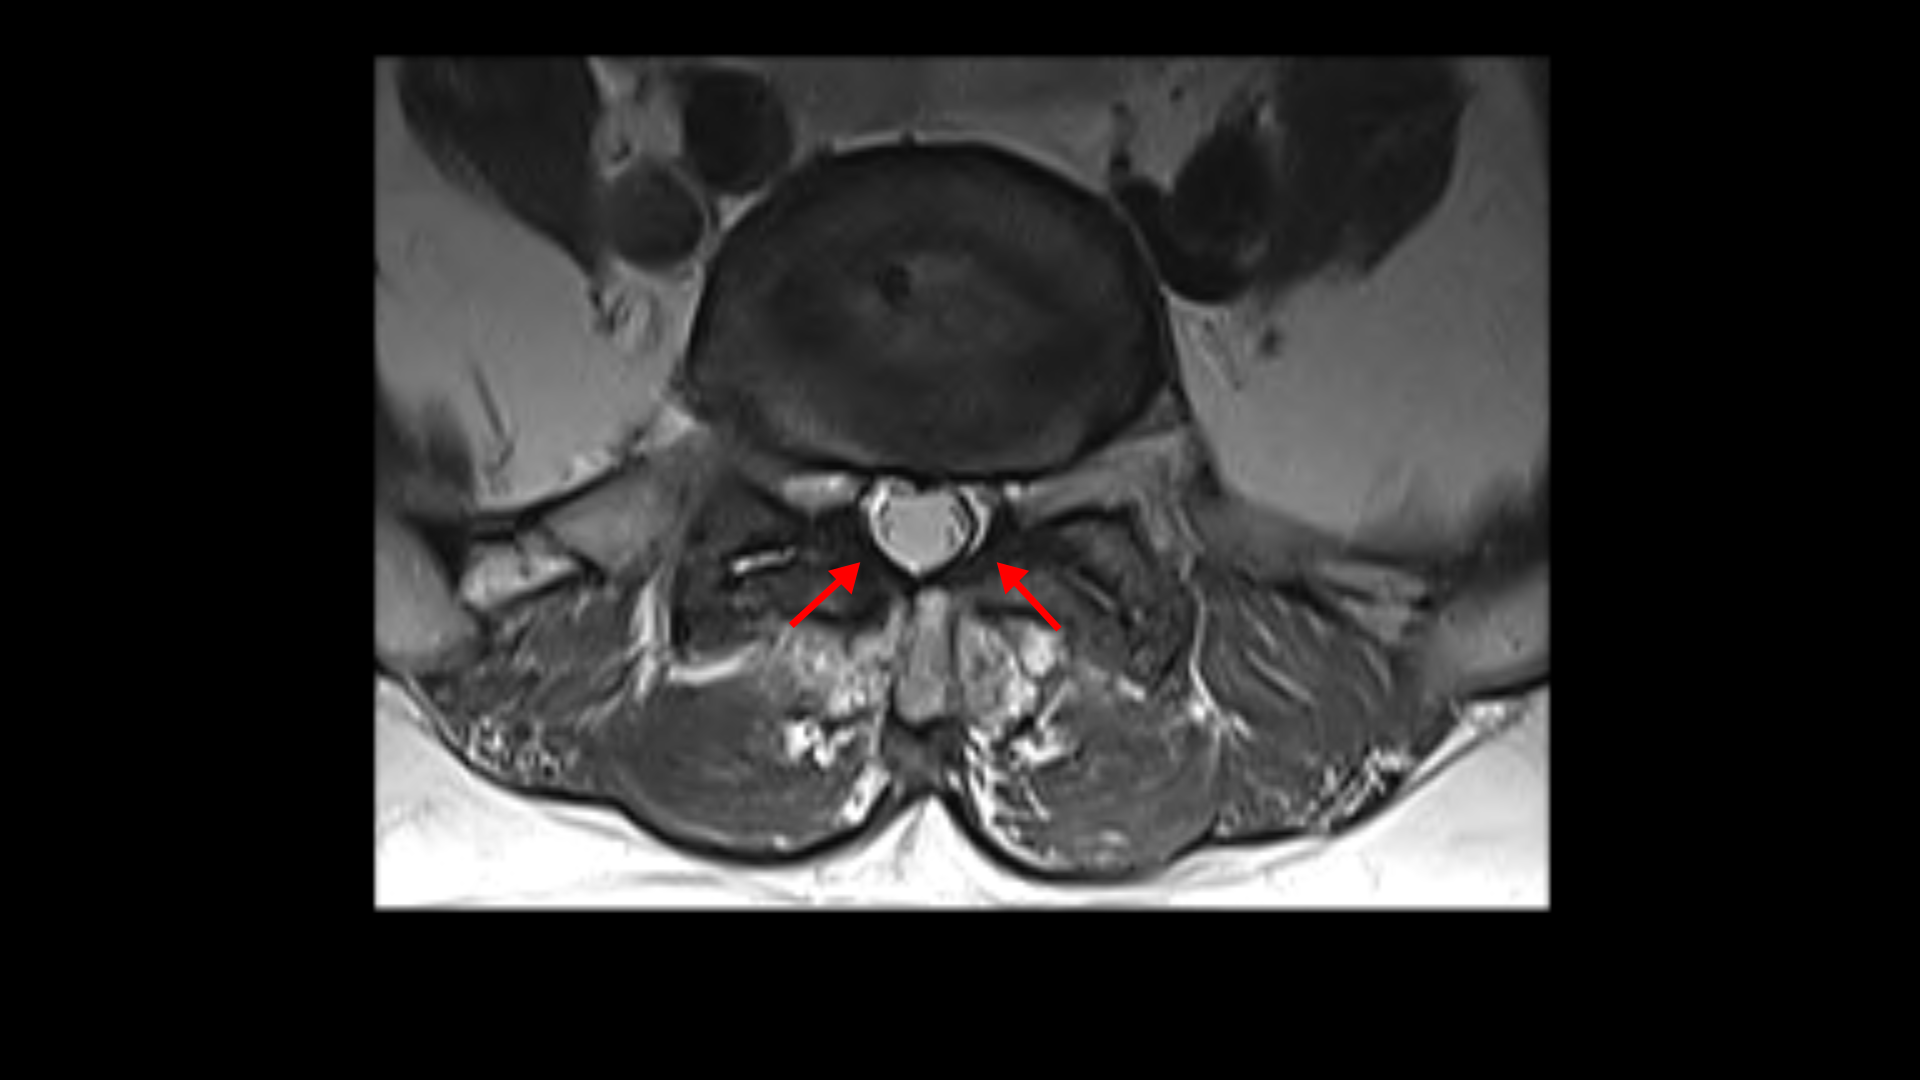

먼저 5번 1번에 척추관 내의 황색인대의 골화 현상이 보이고

후관절의 퇴행도 심해 보입니다.

그리고 허리 4마디에 퇴행성 허리디스크가 있습니다.